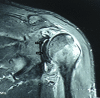

Irreducible shoulder dislocation is an uncommon event. When it does occur, blocks to reduction can include bone, labrum, rotator cuff musculature, or tendon. Concomitant rotator cuff tear at the time of initial dislocation is not an exclusive complication of anterior shoulder dislocation in the older population. Indeed, rotator cuff tear should not be excluded based solely on the patient's age. Rotator cuff interposition is not an uncommon complication after anterior dislocation of the shoulder. It should be suspected when there is incongruency of the joint and persistent subluxation on postreduction radiographs. If such incongruence or subluxation is seen, a computed tomographic (CT) or magnetic resonance imaging (MRI) scan must then be obtained to determine the nature of the interposed soft tissues. The key to treatment is early diagnosis and adequate imaging. Open reduction and repair of the rotator cuff should be performed. We present a technique for treating irreducible anterior shoulder dislocation caused by interposition of the subscapularis tendon. Both CT and MRI observations, along with intraoperative findings and surgical technique, are discussed.